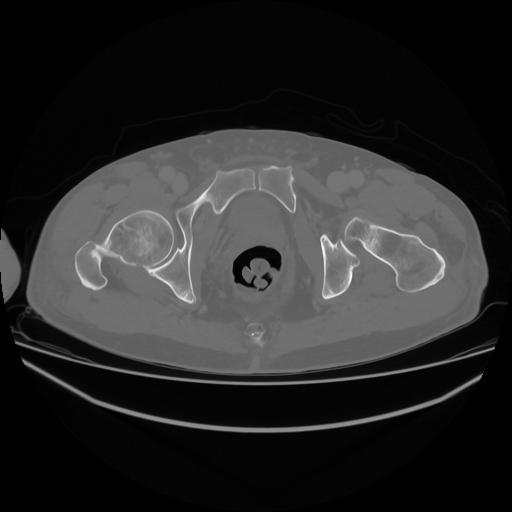

5 CUERPO,CE,Vol,1.0,CUERPO,,